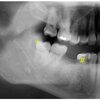

Deep caries destroying the crown to bone level on X-ray – diagnosis?

• Caries dentis profunda non restaurabilis

• (deep non-restorable caries). Treatment: Extraction

* Caries dentis profunda non restaurabilis * (Deep non-restorable caries) → Crown destroyed to bone level